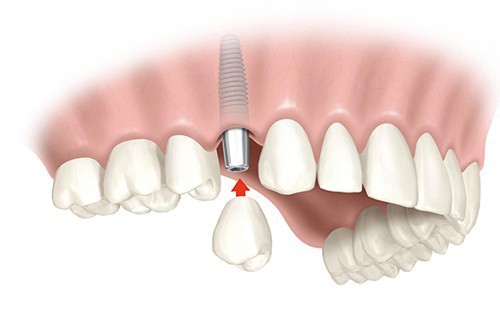

Установка имплантатов

Этот этап и является непосредственно операцией. Через прокол в тканях десны и кости устанавливается имплантат, на котором закрепляется абатмент, а затем – протез. Занимает эта процедура несколько часов, в зависимости от количества устанавливаемых имплантатов и сложности операции.